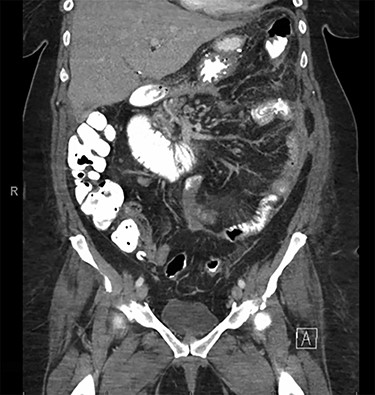

The patient is a 46-year-old female with a pre-operative body-mass index (BMI) of 48 kg/m2 who underwent an uneventful laparoscopic RYGB with a 50-cm biliopancreatic limb and 100-cm alimentary limb and an antecolic, antegastric-stapled gastrojejunostomy using a 21–3.5-mm circular stapler in addition to the repair of a small sliding hiatal hernia. A thick omentum was divided in the midline, starting at the level of the mid-portion of the transverse colon moving distally through the edge of the omentum (Fig. 1). The procedure was uneventful, and the patient was discharged home on postoperative day 1. She had a scheduled follow-up visit at 2 weeks and was progressing as expected. Three weeks postoperatively, she presented to the emergency room complaining of two-day history of severe, diffuse abdominal pain. Initial vital signs were normal and laboratory values were WBC of 6.7 109/L, creatinine 0.76 mg/dl and lactate of 1.2 mmol/L. CT scan was obtained (Fig. 2A and B) that demonstrated 17.7 cm partially encapsulated mixed attenuating area on the right side of her abdomen, suggestive of omental infarction with necrosis. There was no evidence of leak from GJ or JJ anastomoses on CT with oral contrast, which was subsequently confirmed on upper GI with small bowel through. She was admitted for observation. Over the course of the next day, she reported worsening abdominal pain and developed tachycardia to 117 and BP of 89/68 mmHg. Repeat WBC count was 12.7 109/L, creatinine 1.29 mg/dl and lactate of 5.0 mmol/L.

A and B: Abdominal and pelvic CT scan obtained at POD # 21 readmission for abdominal pain showing a 17.7-cm mixed attenuating lesion extending anterior to the transverse colon into the upper-pelvis-associated stranding and fluid level suggestive of omental infarction and liquefied necrosis.